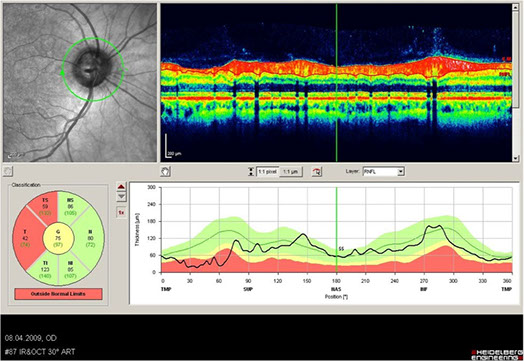

Beim Glaukom (grüner Star) handelt es sich um eine langsam fortschreitende, chronische Erkrankung, welche die Nervenfasern des Sehnervs zerstört. Weltweit sind ca. 67 Millionen Menschen betroffen und ca. 15% aller Erblindungen können auf das Glaukom zurückgeführt werden. In Deutschland ist das Glaukom nach der altersbedingten Makuladegeneration die häufigste Erblindungsursache. Wird das Glaukom jedoch frühzeitig erkannt, so kann man ein Fortschreiten der Erkrankung verhindern und somit meist ein gutes Sehvermögen erhalten.

Der Erkrankung liegt in den meisten Fällen ein erhöhter Augeninnendruck zugrunde. Es gibt jedoch auch Glaukome bei „normalen“ Augeninnendruckwerten. Man spricht hier vom Normaldruckglaukom. Daher ist es wichtig nicht nur den Augeninnendruck zu messen sondern auch den Sehnerv zu beurteilen.

Aufgrund der krankheitsspezifischen Zerstörung der Sehnervenfasern und Nervenzellen (Ganglienzellen) der Netzhaut kommt es im weiteren Verlauf zu einer Störung der Sehfunktion. Die Störung der Sehfunktion äußert sich zunächst durch Ausfälle im Gesichtsfeld, die erst spät, häufig zu spät wahrgenommen werden. Die ersten Gesichtsfeldschäden entstehen in den Randbereichen des Gesichtsfeldes, die volle Sehschärfe bleibt zunächst unverändert gut erhalten. Im weiteren Verlauf der Erkrankung kommt es zu einem zunehmenden Untergang von Sehnervenfasern und schließlich zur unwiederbringlichen Sehverschlechterung.

Heutzutage stehen dem Augenarzt verschiedene, Laser-gestützte, diagnostische Geräte zur Früherkennung eines Glaukoms durch Scannen des Sehnervs zur Verfügung.

In unserer Praxis kann dies durch die optische Cohärenztomographie (OCT) oder den Retinal Thickness Analyser (RTA) erfolgen.

Durch derartige Spezialuntersuchungen können Frühformen eines Glaukoms erkannt und somit eine Sehverschlechterung verhindert werden. wir vermessen Ihren Sehnerv mykrometergenau (1/1000 Millimeter) vermessen lassen um im Verlauf eine mögliche Verschlechterung frühzeitig zu erkennen.